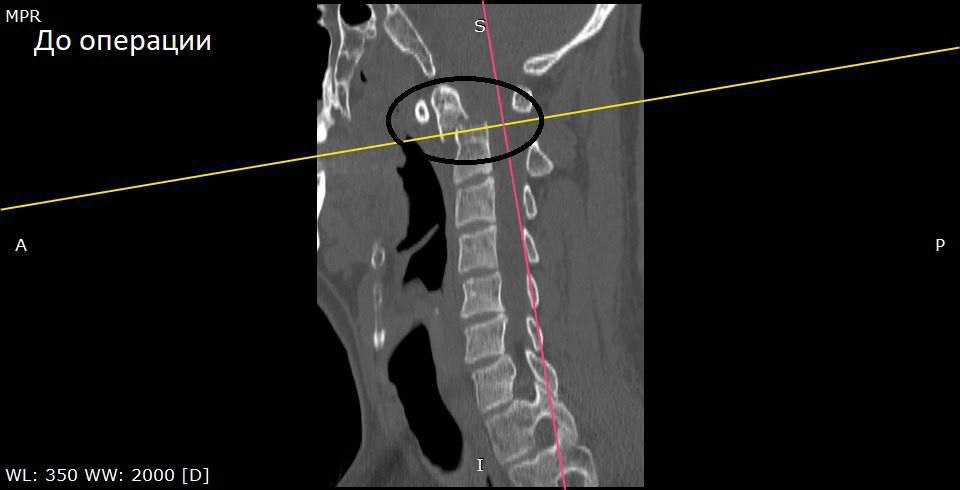

Мужчину госпитализировали. Врачи обследовали шейный отдел позвоночника и выявили перелом второго шейного позвонка (С2) со смещением отломка. Специалисты решили провести операцию — окципитоспондилодез («закрепление повреждённых позвонков верхнего шейного отдела. Позвонки и кости черепа соединяют в единый блок с помощью специальных креплений». — Прим. «Ё!»).

Фото: БУЗ ВО ВГК БСМП № 1